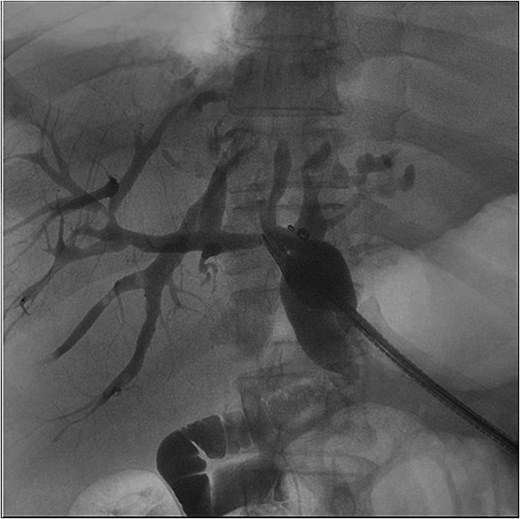

A 62-year-old male presented with the chief complaints of fevers, fatigue, and body aches for one week. He reports an ostomy placed fifteen years prior to, “drain the rocks from my liver.” He reports that stones drained from the ostomy for two years after it was placed. Physical exam was notable for abdominal incisions and left upper quadrant ostomy. Initial workup found a WBC count of 14 000×103/μl, alkaline phosphatase of 571 U/L, and normal bilirubin. Given his vague abdominal pain and fevers, a contrasted computed tomography (CT) scan of the abdomen was performed. This confirmed that the ostomy was a conduit from the biliary tree to the skin. It additionally found a 6.6 × 6.4 cm intrahepatic abscess (Fig. 1). He was admitted and was started on IV antibiotics. Gastroenterology (GI) and Interventional Radiology (IR) were consulted for endoscopic or image-guided drainage, but these were deferred given the tortuosity of his conduit and lack of a safe window, respectively. Given he had improved on antibiotics, it was deemed that operative intervention was not indicated at that time. He was transitioned to oral antibiotics, scheduled for outpatient endoscopic retrograde cholangiopancreatography (ERCP) to better delineate the biliary anatomy, and discharged. Of note, this institution’s policy is that Advanced Endoscopists perform ERCPs. At this time, there are no surgeons who performed ERCPs.

Initial CT scans. (A) Axial images progressing from superior to inferior. These show the hepatic abscess as well as the small bowel limb anastomosed to the biliary tree. (B) The same scan, but in a coronal view. (C) The same scan, but from a sagittal view. This view again illustrates the limb of a small bowel anastomosed to the biliary tree. Surgical clips are seen in the gall bladder bed.